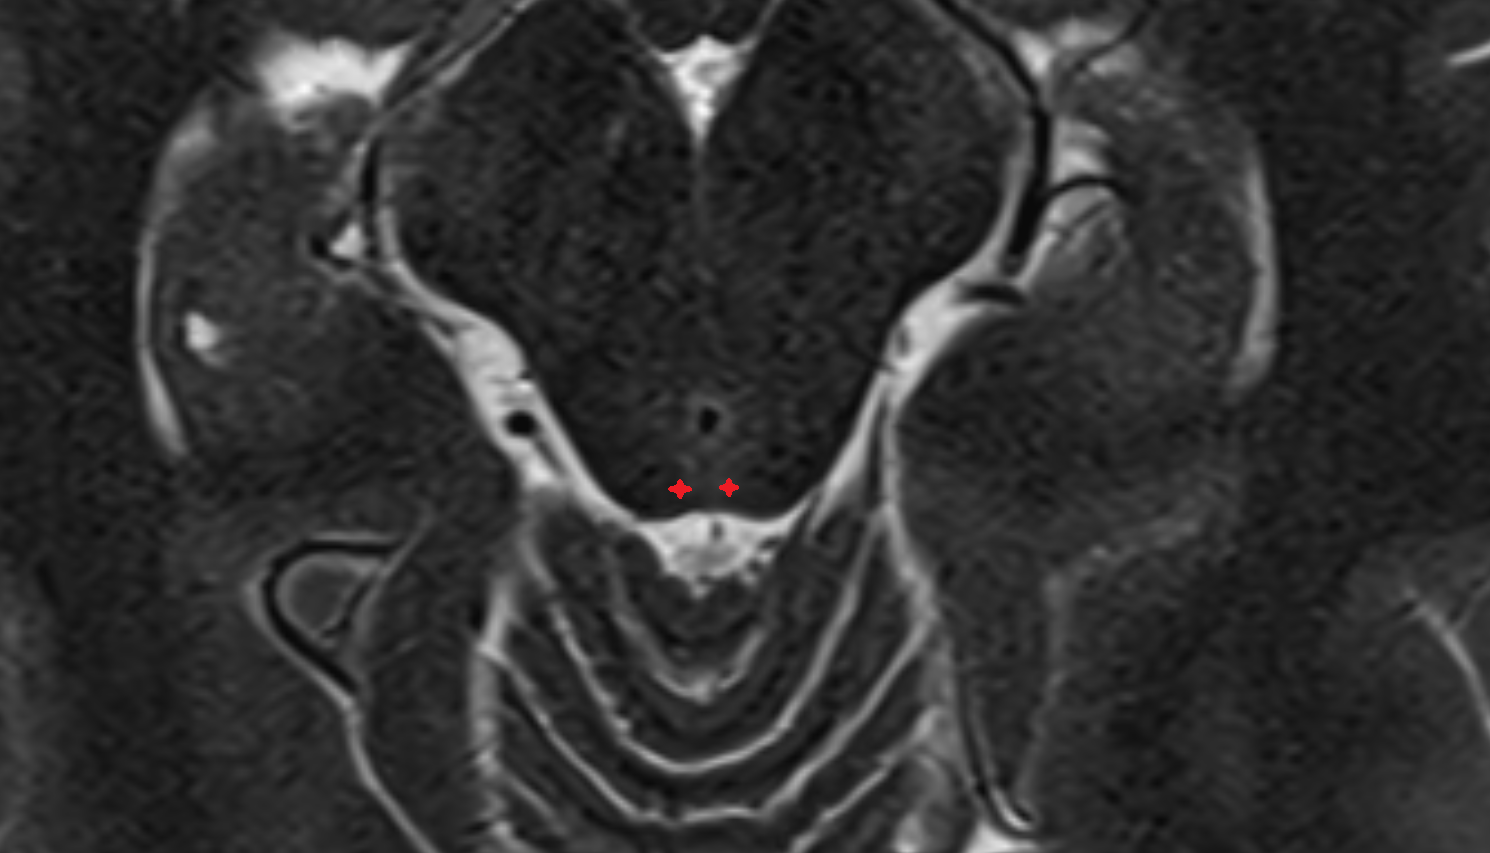

- Hippocampus